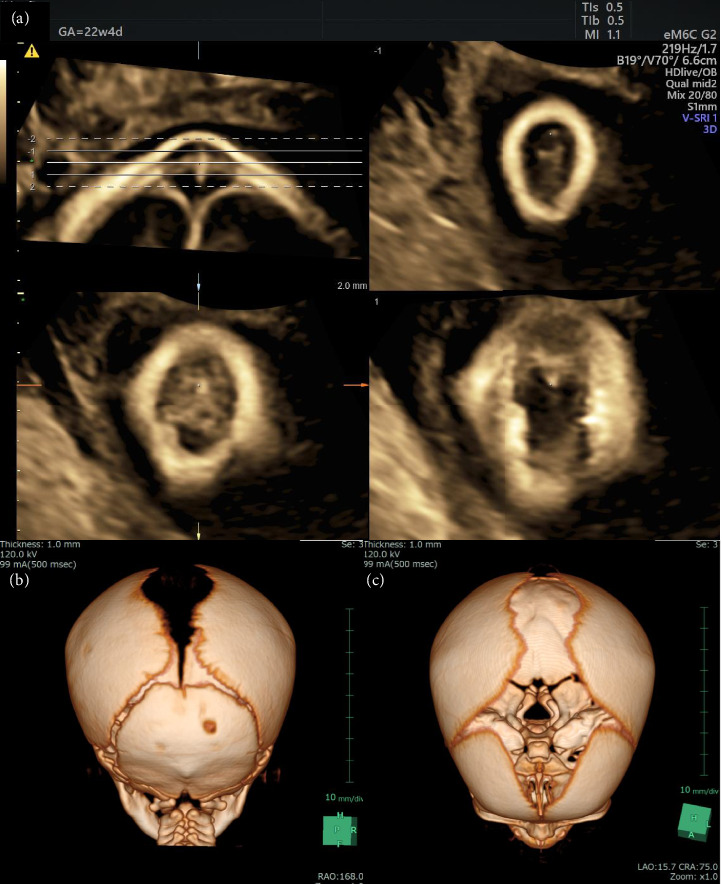

Determining the differential diagnosis of small scalp cysts identified on a fetus is difficult. In particular, many physicians have difficulty differentiating small meningoceles from small scalp cysts during the prenatal period. Volume contrast imaging increases contrast between tissues, thereby allowing an enhanced view of target structures. A 15 × 5 mm scalp cyst was identified on a fetus during a prenatal ultrasonography examination performed at 20 weeks of gestation. The cyst was not connected to the blood flow, and did not include the tissue of the brain parenchyma. Ventriculomegaly and other structural abnormalities were not observed. Based on these findings, we suspected a sinus pericranii or fetal epidermal cyst. The size of the fetal scalp cyst was stable, and the growth of the fetus remained normal until birth. The diagnosis of a small meningocele was confirmed postnatally, based on the results of a magnetic resonance imaging examination. Postnatal evaluation of offline volume contrast imaging of prenatal three-dimensional ultrasound data at 22 weeks of gestation revealed a skull bone defect beneath the cyst. Volume contrast imaging can facilitate the prenatal diagnosis of small meningoceles by detecting bone defects on the fetal head.

Abstract Image